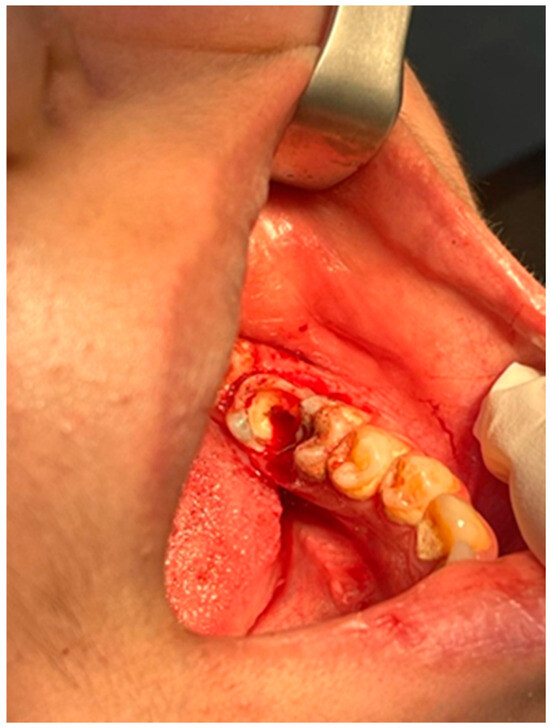

2.4. Surgical Management